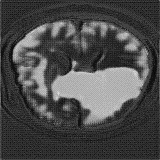

We obtain a subject-wise mean Dice score of 63.67% for the brain tumor segmentation. Utilizing a simple post-processing scheme of erosion and dilation with filter, we improve our mean Dice score to 68.01%. Figure 4 shows samples generated by our ASC-Net and Table 2 shows our before and after post-processing results. We attempted to apply f-AnoGANs [34] by following their online instructions and failed to generate good reconstructions as shown in Figure 5. The failure of AnoGANs in the reconstruction brings to light the issue with the regeneration based methods and the complexity and stability of GAN-based image reconstruction.

We obtain a subject-wise mean Dice score of 32.94% without any post-processing. By using a simple post-processing with erosion and dilation with filters, this number improves to 48.20% mean Dice score. In comparison, a similar study conducted by [3] consisting of a multitude of algorithms including AnoVAEGAN [4] and f-AnoGANS, obtained a best mean score of 27.8% Dice after post-processing by f-AnoGANS. Before post-processing the best method was Constrained AutoEncoder [8] with a score of 9.7% Dice. An exhaustive list is presented in Table 1. Figure 4 shows sample images of our results.

We obtain a slice-wise mean Dice score of 32.24% for this liver lesion segmentation, which improves to 50.23% by using a simple post processing scheme of erosion and dilation with filter. Sampled results are shown in Fig. 4. Compared with [42], which obtains a mean Dice score of 40.78% and a standard deviation of 0.43%, we improve the mean Dice score by almost 10%, but has a much larger standard deviation. Unlike [42], where the network is pre-trained on a artificial tumor dataset, and hence the pipeline customized for tumor segmentation, our method do not need such information beforehand. We notice that our standard deviation for BraTS dataset is similar to [27]. This is because novelty/anomaly detection algorithms without a pre-defined task would suffer from the co-morbidities issues discussed in Section 5.